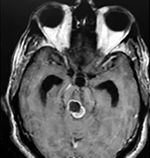

Paciente femenino de 29 años de edad con historial de cefalea crónica que presenta súbitamente disdiadococinesia y dismetría izquierda.

El estudio de RMN presenta una lesión bien circunscrita en hemisferio cerebeloso izquierdo con periferia de predominio hiperintenso en T1 y T2, y centro hipointenso, edema perilesional mínimo, así como una imagen de un vaso venoso alimentador que recorre hacia el ángulo pontocerebeloso izquierdo.

El estudio de control de RMN se observa la brecha quirúrgica y ausencia de lesión (figs. 1, 2 y 3).

Lesión cerebelosa izquierda ponderaciones en T1 y T2, la flecha señala vaso nutricio hacia el ángulo pontocerebeloso izquierdo, se puede observar el centro de intensidad heterogénea con contenido quístico multiloculado y edema perilesional leve.